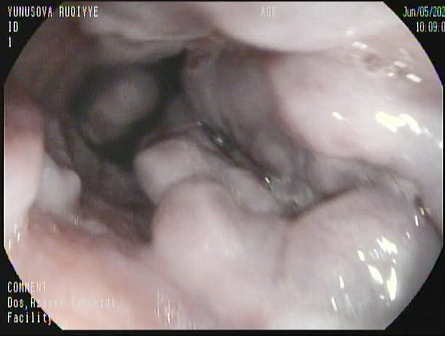

Резюме. Варикозное кровотечение составляет 10% от всех кровотечений из верхних отделов желудочно-кишечного тракта. Лечение варикозного кровотечения затруднительно, в некоторых случаях наблюдается рецидив кровотечения, вплоть до летального исхода. При отсутствии терапевтического (эндоскопического) вмешательства рецидив кровотечения(ий) возникает(ют) в течение первых 6 недель. Варикозное расширение вен желудка (ВЖ) встречается реже (20%), чем варикозное расширение вен пищевода (ВП). Кровотечение возникает у 4-65% пациентов с портальной гипертензией (ПГ) в течение 2 лет после постановки диагноза. Диагноз ВЖ более серьезен, имеет риск интенсивного кровотечения и осложнений. Поэтому оптимальный процесс лечения кровотечения из ВЖ постоянно совершенствуется. В последние годы в литературе при гастро-эзофагeальных кровотечениях (ГЭК) рекомендуется банд-лигация при варикозном расширении вен пищевода, а при ВЖ эндоскопическое применение оптимальных облитерирующих препаратов (тканевых клеев) - N-бутилцианоакрилата (Глубрана-2) рассматривается как малоинвазивный и оптимальный метод лечения. Выбор эндоскопической тактики при кровотечениях варикозного генеза заключается в изучении того, какие вены варикозно расширены и когда следует проводить вмешательства в первую очередь, в зависимости от локализации кровотечения. Эндоскопическое лечение с банд-лигированием и введением Глубрана-2 было проведено 116 пациентам с кровотечением из верхних отделов желудочно-кишечного тракта. Пациенты были разделены на 3 группы: I группа – кровотечение из ВП и риском кровотечения из ВЖ – 55; II группа – ВП с риском кровотечения и кровотечение из ВЖ – 24; III группа –ВП и ВЖ с риском кровотечения – 37 пациентов. У этих пациентов изучались рецидивы кровотечения, осложнения и оптимальные сроки склерозирования. Средний возраст в группах составил 59,8 ± 9,6, соотношение М:Ж было 70:46, а средний период наблюдения составил 409,6 ± 202,3 дня. В группе I кровотечение чаще встречалось у пациентов с ВЖ, имеющих риск кровотечения после перевязки ВП - 14-33,3%. У этих пациентов портальное давление увеличивалось после перевязки ВП, и вследствие гипертензии происходил разрыв и возникало повторные кровотечения из ВЖ. В группе I ВЖ была облитерация в течение 1 недели из-за кровотечения из ВЖ у 7 пациентов, а у 2 пациентов эндоскопический контроль кровотечения оказался невозможным, и они были направлены на TIPS. У 14 пациентов в группе II облитерация ВЖ и банд-лигация ВП выполнялись одномоментно. У 10 пациентов сначала выполнялась облитерация ВЖ, а в течение следующих 3-4 недель – банд-лигация ВП. В группе III сначала выполнялась облитерация ВЖ, а ВП лигировались эластичными кольцами в тот же сеанс. Во всех группах наблюдались такие осложнения, как плеврит, язва после лигирования, спонтанный бактериальный перитонит, пневмония, асцит и энцефалопатия. Заключение: 1. Варикозное расширение вен пищевода и желудка является распространенной проблемой в медицине и считается одной из основных причин смерти при кровотечениях из верхних отделов желудочно-кишечного тракта. 2. Независимо от локализации кровотечения, эндоскопическое вмешательство следует выполнять в первую очередь в места кровотечения. 3. Банд-лигация считается наиболее оптимальным методом при варикозном расширении вен пищевода, а облитерация тканевым клеем – при варикозном расширении вен желудка. 4. При наличии риска кровотечения из варикозно расширенных вен пищевода и желудка рекомендуется проводить вмешательство одномоментно. 5. При кровотечении из вен пищевода не проводится лигация желудочных вен, поскольку в это время возрастает риск рецидива кровотечения из лигированных вен пищевода.